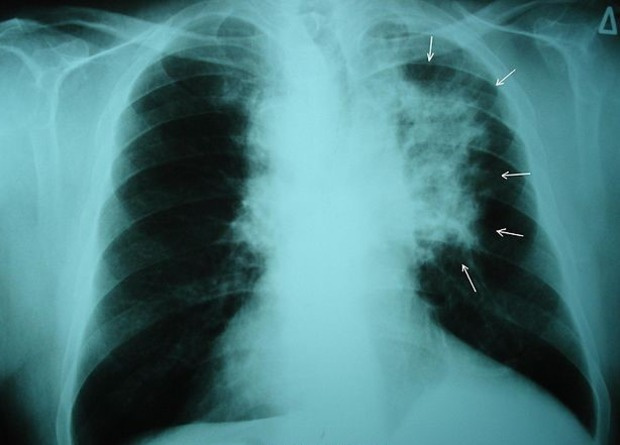

Метаанализ девяти исследований показал, что скрининг на рак легких снижает смертность от него на 16 процентов. Метаанализ выполнили британские врачи, которые наряду с другими работами включили в него также результаты проведенного ими скрининга в британской когорте. Несмотря на то, что в группе скрининга в этом исследовании умерло меньше людей, чем в контрольной группе, разница оказалась статистически незначимой. Работу опубликовали в The Lancet Regional Health — Europe.

Ежегодный скрининг среди предрасположенных к раку людей проводят для многих видов злокачественных образований, но не всегда понятно, можно ли предотвратить смерти от рака, если диагностировать его на ранней стадии. Так британские ученые обнаружили, что скрининг, определяющий онкомаркер рака яичников, не снижает смертность от этого заболевания. В то же время для рака легких лучевые методы диагностики на ранних стадиях заболевания, по всей видимости, помогают снизить смертность — такие результаты получили исследователи, которые проводили периодический скрининг на когорте датчан и бельгийцев.